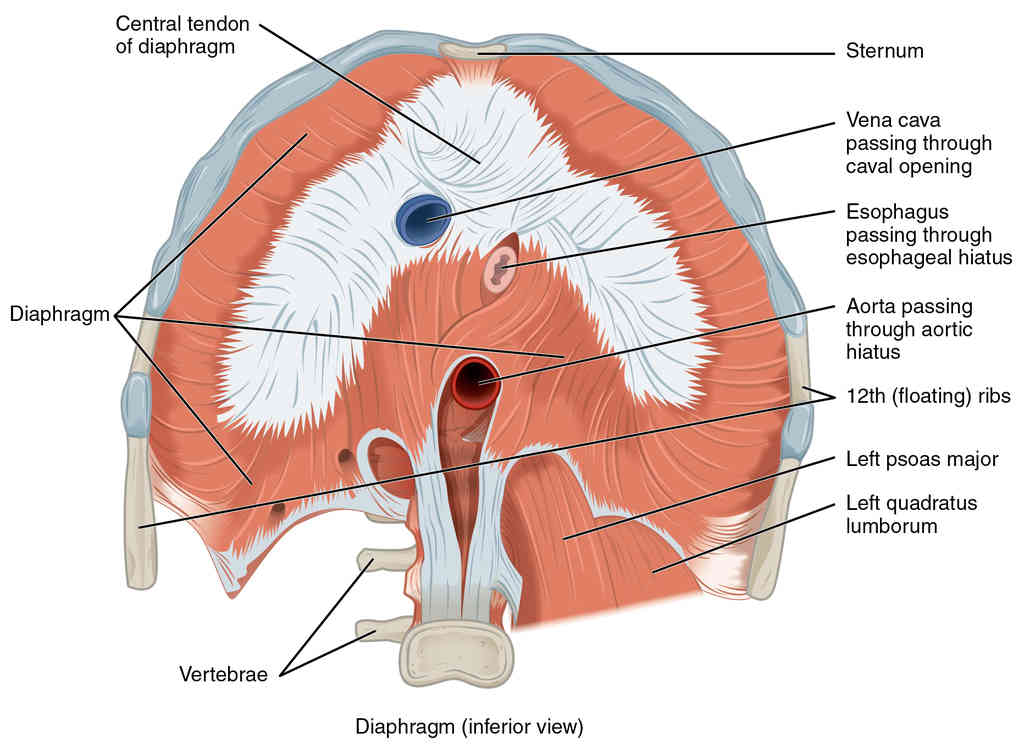

This page is under construction. For now, it is just a resource of the images found in the OpenStax Anatomy and Physiology Handbook. It wil slowly change into a revision tool. Each slide has a number. Use this to refer to the slide. When completed, it will have an unlabelled section, with labelled slides in parallel. On the unlabelled slides, write your answer and use the labelled slide to assess yourself. Keep track by also noting the number on each slide. Improvement at each attempt is important, more so than full marks on a first attempt.